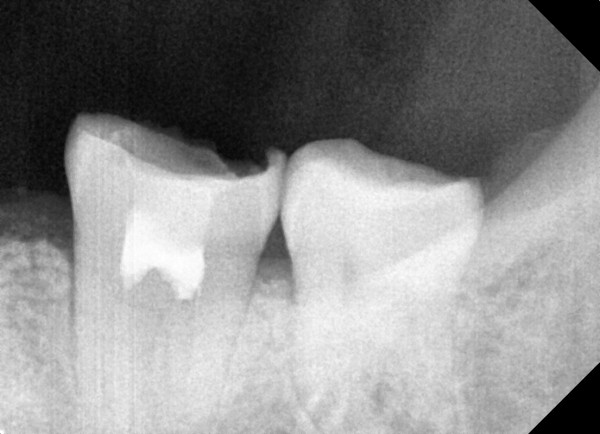

충치치료&신경치료 하루에 끝나는 신경치료

ab84f1a97a55df0651436bf31adcdd0f_1767396742_2926.jpg

ab84f1a97a55df0651436bf31adcdd0f_1767396742_2725.jpg

c36d6f431fa4d39e6efca10cb66686a2_1767334359_1857.jpg